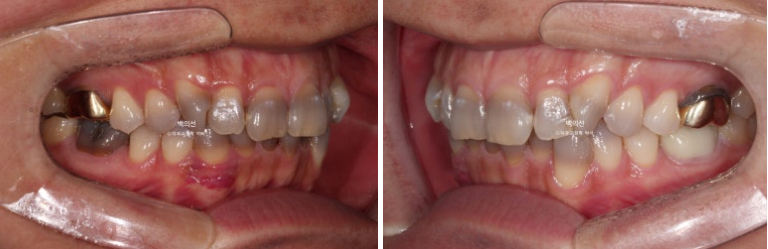

However, as you can see from the front, the canine crowding means laminate treatment would be difficult unless orthodontic treatment is done first.

The canine crowding is fairly severe.

Before the no-prep laminate, we decided to first proceed with non-extraction canine crowding correction using CLIPPY-C.

The space needed to align the crowded teeth was to be obtained by moving the molars backward using the wisdom tooth space.